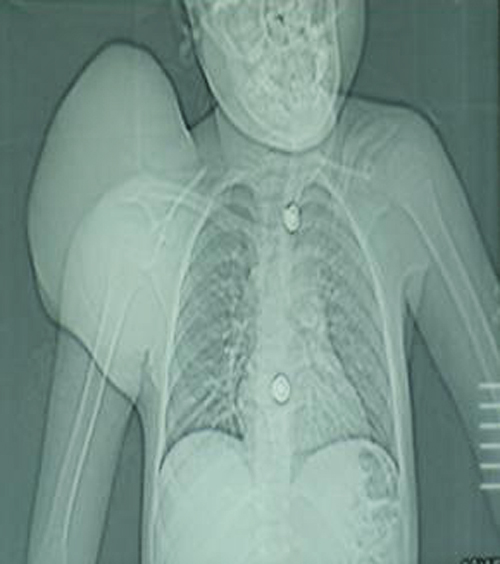

phosphatase were within normal limits. X-ray and CT scan of the scapular region

showed soft tissue swelling without any bony involvement (Fig. 2,3). Fine needle aspiration suggested malignant soft tissue tumour. Incisional biopsy confirmed the diagnosis of ES. The

Figure 2:

CT scout view showing soft tissue shadow

Figure 3:

CT scan showing soft tissue tumour

of X-ray and CT scan of our case showed the tumour as

soft tissue swelling over scapular region. Molecular and cytogenetic analysis